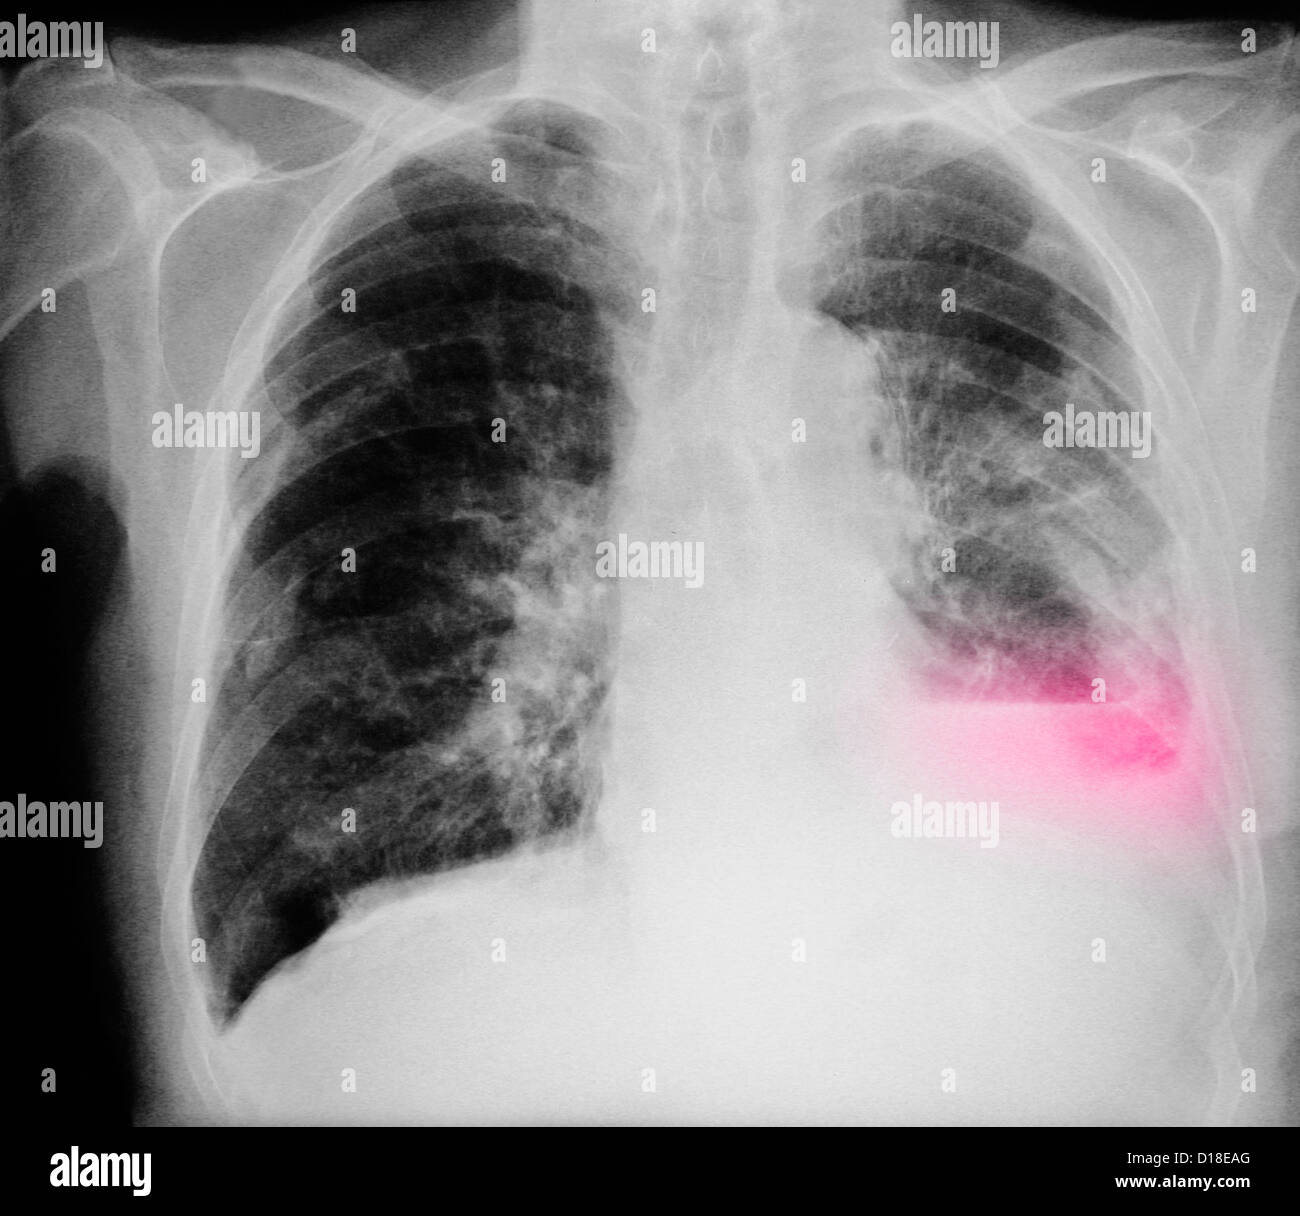

From www.alamy.com

xray showing lung cancer in an 80 year old man with a long history Stock Photo, Royalty Free How Long Can An 80 Year Old Live With Lung Cancer recommended treatment options can vary for older people with lung cancer, depending on overall health and type of lung cancer. around 5 out of 100 people (around 5%) with stage 4 lung cancer will survive their cancer for 5 years or more after they’re. due to increasing life expectancy and the increased risk of. this rate. How Long Can An 80 Year Old Live With Lung Cancer.

Chest Xray of an 84 year old man with lung cancer Stock Photo Alamy How Long Can An 80 Year Old Live With Lung Cancer around 5 out of 100 people (around 5%) with stage 4 lung cancer will survive their cancer for 5 years or more after they’re. this rate compares a person with a specific type and stage of lung cancer to the general population. recommended treatment options can vary for older people with lung cancer, depending on overall health. How Long Can An 80 Year Old Live With Lung Cancer.